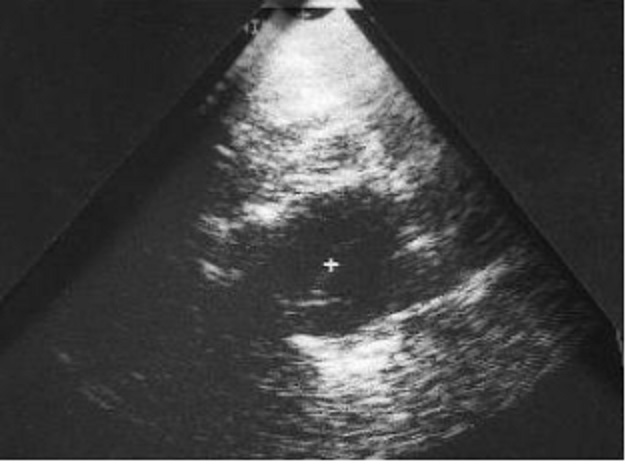

Image echographique d'une

lesion parietal ( metastase costale ) la lesion est

hypoechogen , bord tres nette . Echographie de la

paroi thoracique

permet de verifie la

solidarite

d'une masse ce qui se lier

avec le gril costal ou avec la partie molle du

thorax ou le poumon. La perte du glissement

pulmonaire en échoscopie peut signaler l'extension

au poumon ou

au contraire

l'origine pulmonaire